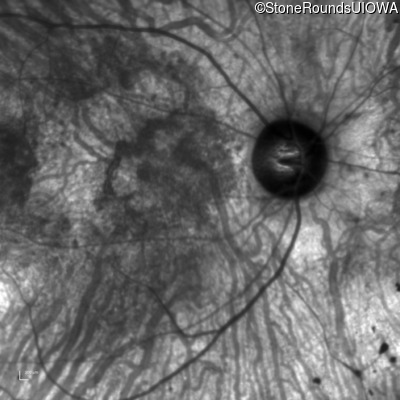

Infrared Fundus Photograph - Right - 20/200 +2

Exemplar